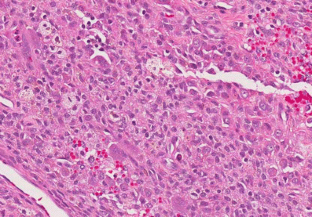

Sikaria, S., Heim-Hall, J., Diaz, E.H. et al. Partial response of a rare malignant metastatic diffuse tenosynovial giant cell tumor with benign histologic features, treated with SCH 717–454, an insulin growth factor receptor inhibitor, in combination with everolimus, an MTOR inhibitor. Targ Oncol 9, 73–79 (2014). https://doi.org/10.1007/s11523-013-0267-8